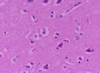

What type of cells are seen and what are their function?

Gitter cells (foamy cytoplasm)

Function: microglia that ingest myelin debris